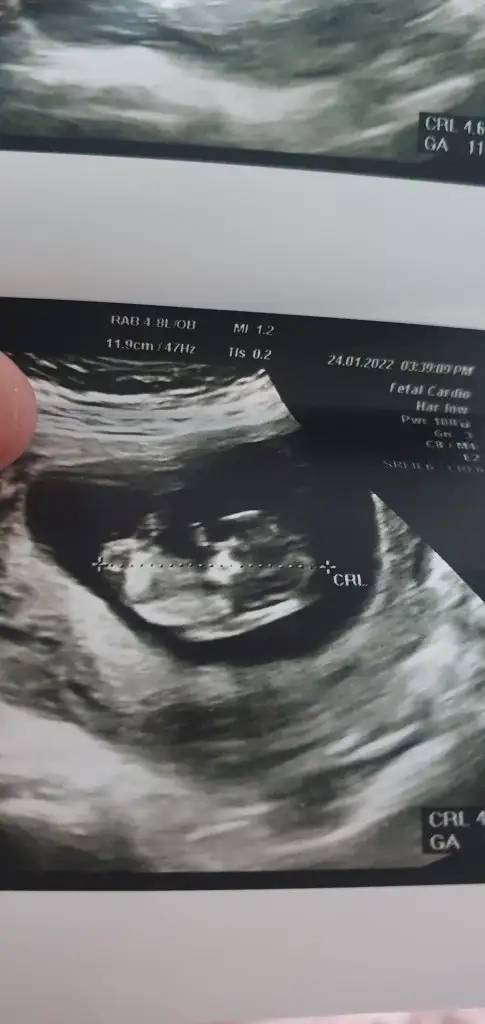

Henüz çok küçük biliyorum 11 haftalık olduk tahmin alabilirmiyim... Ikra meyra

• 20220124_155425.webp

40,3 KB · Görüntüleme: 53